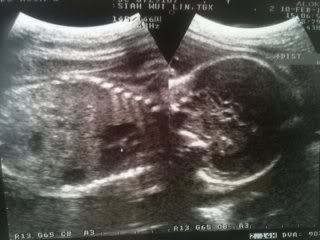

Precious is very big already! Saw her arms, legs, head, body. Her tummy is so round. Cute! She's moving around all the time. Even now! She's becoming more and more active already. Currently I'm into my 29th of pregnancy. Few more weeks and precious will arrive in this world. I'm so anxious! Doctor gave us a scan photo of her. Scroll down to see my little girl! =P

Photo of my lil' girl!